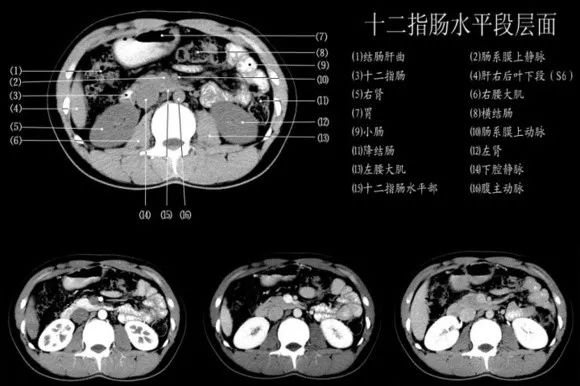

腹部ct太复杂 专家分享干货 手把手教你变身腹部ct高手 胆囊 胰腺 腔静脉 主动脉 肠系膜 网易订阅